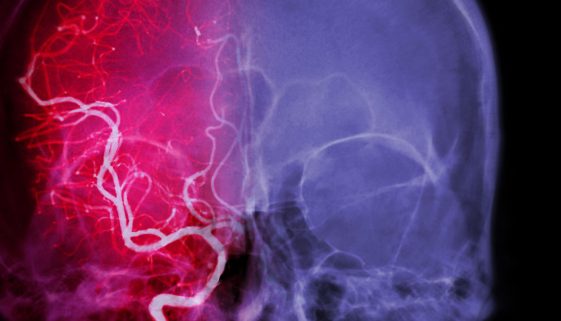

يُعتبر نزيف المخ من الحالات الطبية الطارئة التي تتطلب رعاية فورية وعناية مركزة. يُعرف أيضًا بالنزيف الدماغي، ويحدث عند تمزق أوعية دموية داخل المخ، مما يؤدي إلى تجمع الدم. هذا التجمع يزيد من الضغط على أنسجة المخ، ويؤدي إلى تلف الخلايا. في هذه المقالة، سنستعرض النصائح والتعليمات التثقيفية بخصوص علاج […]